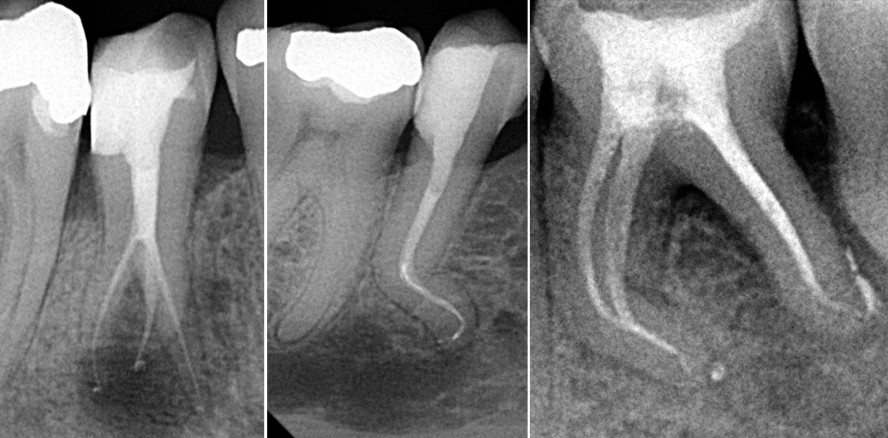

In geraden Kanälen gestaltet sich die Umsetzung jener Prinzipien unkompliziert, größere Probleme entstehen erst bei stark gekrümmten Kanälen, Verästelungen oder Anastomosen (Abb. 1). In solchen Fällen kann es schwierig sein, die grundlegenden Endo-Techniken und Behandlungsprotokolle einzuhalten. Zur sicheren, zuverlässigen Instrumentierung kann nun eine neuartige NiTi-Feilensequenz in der sogenannten TCA-Technik angewendet werden.

Dies führt wiederum oft zur Verringerung des Krümmungswinkels, Verkürzung der Länge, Vergrößerung des Radius und Verschiebung der Kurve apikal (Abb. 2). In stark gekrümmten Kanälen ist eine kleinere apikale Aufbereitung aus zwei Gründen zu präferieren: